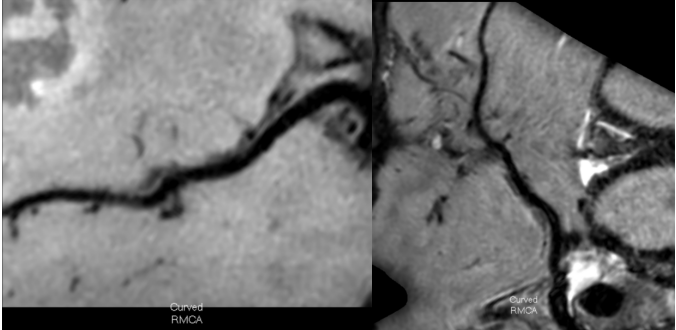

3招丨找出壁间血肿(动脉夹层)

1 TOF-MRA图可见颈内动脉内膜片影

2 CE-MRA图可见颈内动脉真假腔显示

266bdc3b78e99e1e45b42d871817ee31.png

13D-T1-SPC图显示打药前颈内动脉C1C2段高亮的壁间血肿及管腔重度狭窄。

23D-T1-SPC图显示打药后血肿及相应节段血管壁都强化不明显。